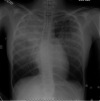

Observations: The authors present the case of a 14-year-old patient 8.2 years after CRT who experienced intracerebral hemorrhage. Autopsy demonstrated minimal pathological change without evidence of vascular malformation or aneurysm. These findings were unexpected given the degree of hemorrhage in this case. However, in the absence of other etiologies, it was believed that late-delayed radiation effect was the cause of this patient's fatal hemorrhage.